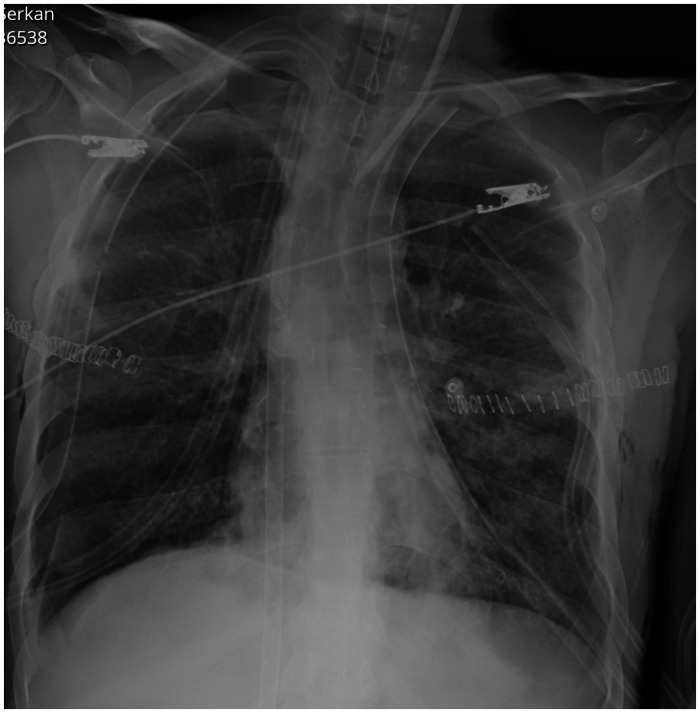

囊性纤维化患者可考虑肺移植。尽管与其他患者相比,这些患者可能经历更成功的结果和生存率,但可能出现各种并发症。特别是,感染性并发症和脓毒性死亡在囊性纤维化患者中可能比其他肺移植适应症更普遍。考虑到所有这些因素,识别和处理该患者组术后可能出现的并发症至关重要。在这篇文章中,我们按时间顺序介绍了一例因囊性纤维化而接受肺移植的患者在移植后发生的多种危及生命的并发症,并对其处理进行了讨论。

Cystic fibrosis patients may be considered for lung transplantation. Although these patients may experience more successful outcomes and survival rates compared to others, various complications can arise. In particular, infectious complications and septic deaths may be more prevalent in cystic fibrosis patients compared to other lung transplant indications. Considering all these factors, recognizing and managing complications that may arise during the postoperative period in this patient group are of critical importance. In this article, multiple life-threatening complications occurring in the post-transplant period in a patient who underwent lung transplantation due to cystic fibrosis are chronologically presented, and their management is discussed.